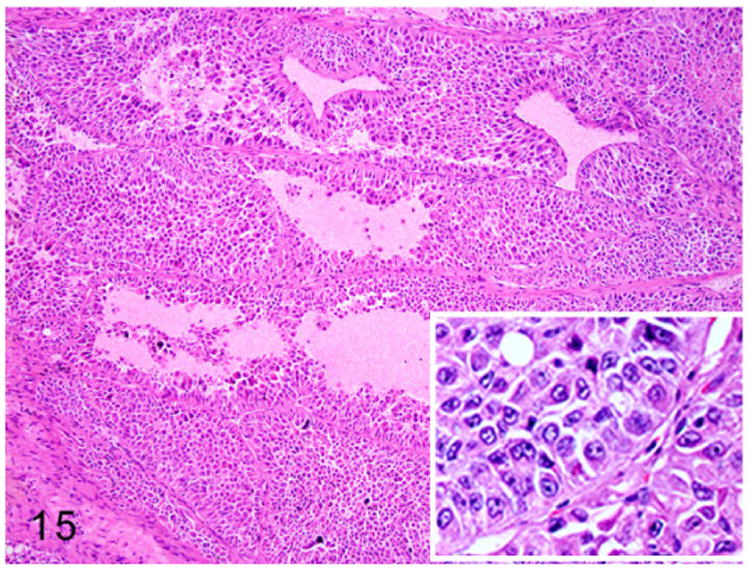

Sertoli cell tumors are occasionally reported in middle-aged male ferrets.7,41,120 These tumors are unilateral or bilateral and enlarge the affected testes. Sertoli cell tumors arise from the sustentacular cells of the seminiferous tubules. On gross examination, these tumors are firm, pale tan, and compress the adjacent normal testicular parenchyma. Microscopically, these neoplasms are composed of elongate polygonal cells arranged in sheets and irregular tubules supported by moderate fibrovascular stroma. Neoplastic cells palisade along the basement membrane and fibrous stroma (Fig. 15). The neoplastic cells have distinct cell borders and scant to moderate vacuolated granular eosinophilic cytoplasm (Fig. 16). Nuclei are round to oval with stippled chromatin and distinct small basophilic nucleoli. Adjacent testicular parenchyma has extensive areas of necrosis, hemorrhage, and atrophied seminiferous tubules. Metastasis of a Sertoli cell tumor to the liver has been reported in a ferret.120

Figure 15.

Sertoli cell tumor, testis, ferret. Tubular structures are composed of multiple layers of neoplastic cells. The neoplastic cells are arranged perpendicular to the basement membrane (inset). HE.

Figure 16.

Higher magnification of Fig. 15. Neoplastic cells palisade around blood vessels. The elongated polygonal neoplastic cells have abundant eosinophilic granular cytoplasm with intracytoplasmic vacuoles. HE.